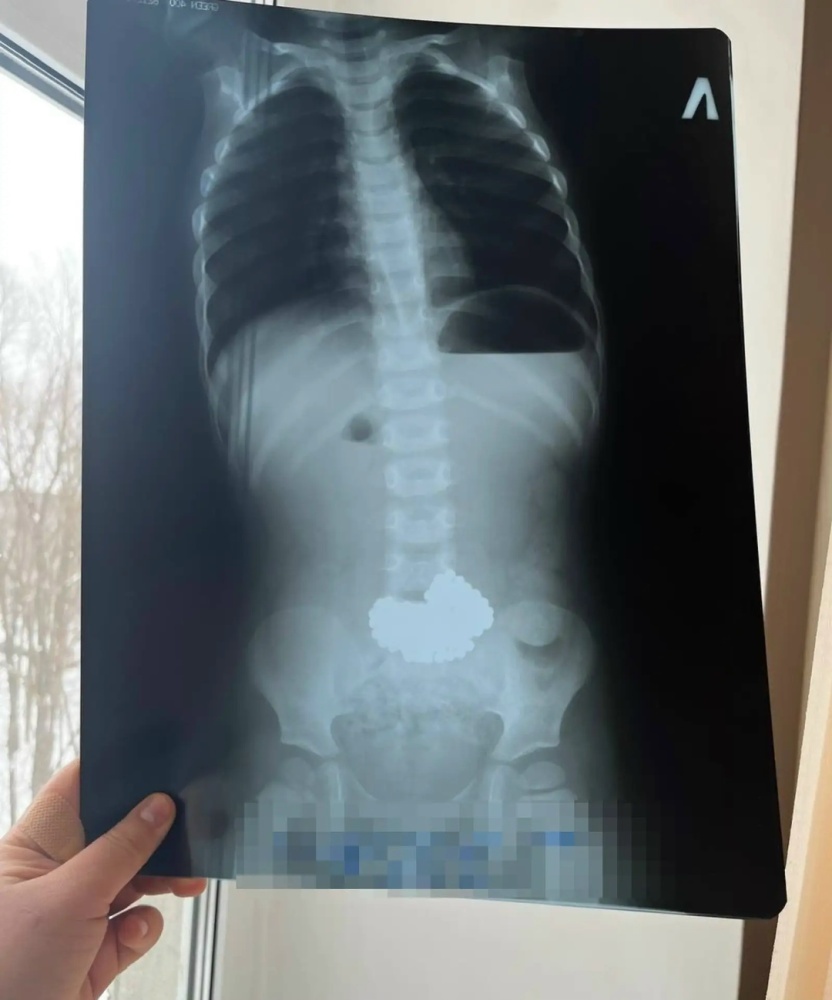

В Нефтекамске трёхлетний ребёнок проглотил 206 магнитных шариков

В Нефтекамске трехлетний мальчик был госпитализирован в реанимацию после того, как проглотил 206 шариков магнитного конструктора. Родители заметили отсутствие игрушек слишком поздно и экстренно доставили ребенка в местную больницу, как сообщает Mash в Башкирии.

Оттуда санитарная авиация доставила маленького пациента в Республиканскую детскую клиническую больницу г.Уфы. Врачи приняли решение об оперативном вмешательстве, во время которого удалили неодимовые шарики-магниты.

Благодаря усилиям врачей ребёнку своевременно оказана медицинская помощь и его жизни сейчас ничего не угрожает.